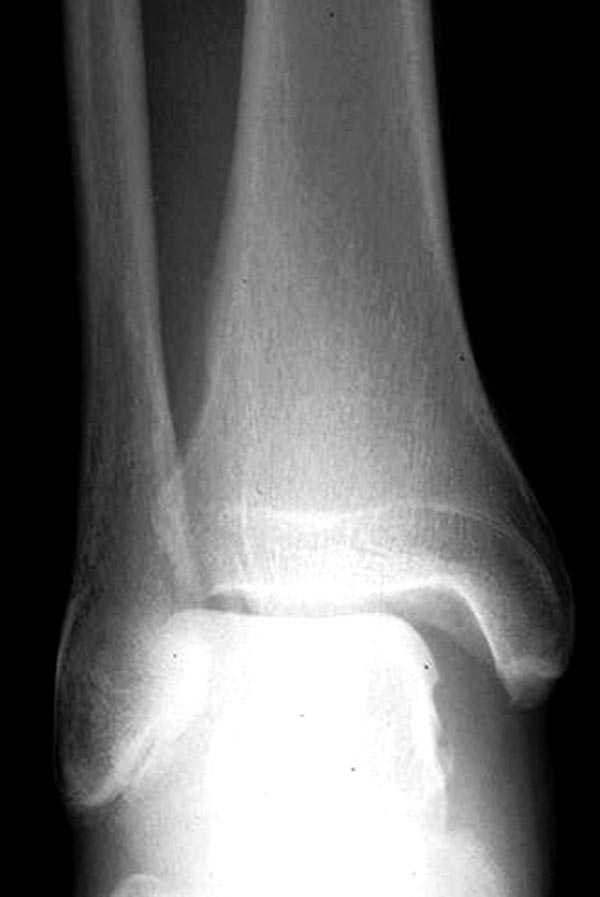

здесь пропускаем повреждение Maisonneuve...

Здесь как раз тот случай, когда рентгеновский снимок скрывает главную проблему. "Ходит, прихрамывая на правую ногу, отмечает боли в правом голеностопном суставе" По описанию клиника типичная для повреждения голонестопного сустава - синдесмоза.

При проксимальных переломах малоберцовой автоматически необходимо подозревать повреждение синдесмоза - Maisonneuve Fracture.

Описанное в 1840 году Maisonneuve повреждение характеризуется тем, что при фиксированной наружной ротации стопы повреждается передняя фибуло-тибиальная связка, часть синдесмоза, с переломом медиальной лодыжки и без, дальше разрыв продолжается по межкостной мембране и спиральный или косой перелом малоберцовой происходит выше.

На прямой проекции можно увидеть расширенную медиальную щель, и на мортизе укорочение малоберцовой.